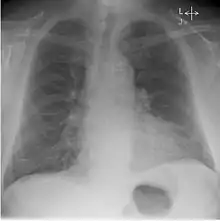

Whilst working at Westminster and the Royal Chest Hospital, Kerley published on the X-ray features of early Pulmonary tuberculosis. As well as his 'B lines' in congestive heart failure he also reviewed X-ray changes in congenital lung diseases, congenital heart disease, intrathoracic aneurysm and bronchiectasis. He gave one of the earliest accounts of chest X-ray and contrast, that is bronchography and lipiodol.[3]

He discovered several of the medical signs used in interpreting radiographs. Famous for his 'B' lines, Kerley B lines are a finding of congestive heart failure.[3] These are short parallel lines perpendicular to the lateral lung surface, indicative of increased opacity in the pulmonary septa. Kerley A lines and Kerley C lines are related findings.[1]